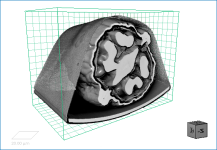

In some cases, you may find it advantageous to apply multiple effects to a visual or visuals. For example, edge contrast and a look-up table.

Multiple effects of edge contrast and a LUT